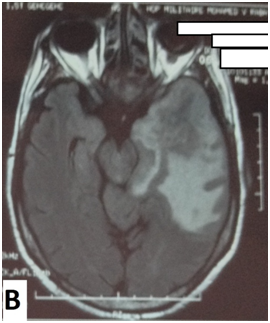

The cerebral MRI showed heterogeneous decreased signal intensity in T1, T2 and Flair-weighted images with variable sizes, surrounded by large area of increased signal intensity in T2 and Flair weighted-images with mass effect on the ipsilateral ventricle (Figure 1). The T1 sequences with intravenous gado injection showed heterogeneous gado enhancement corresponding to the area withT2 and Flair decreased signal intensity (Figure 2). This pattern corresponds to the “swiss cheese” and “soap bubble” aspect. The diffusion weited image showed increased ADC with increased water mobility in left temporal lobe (Figure 3). The radiological conclusion was temporal radionecrosis with large vasogenic edema, or the differential diagnosis of cerebral metastasis of the primary nasopharyngeal carcinoma. Thus, a spectroscopy was performed, and showed decreased peak of N-Acetyl-Aspartate (NAA) and Creatinine (Cr), with normal choline peak. The diagnosis of temporal radio necrosis was established. The patient was proposed to hyperbaric oxygen. His Oto-rhino-laryngeal examination was normal, as much s the chest X-ray. So a daily 45 minutes session, were performed for 10 successive days, associated to bolus of methylprednisolone (240mg/d for 10 days), anti-platelet agent (aspirin 160mg/d). The evolution was favorable, with regression of vestibular signs, improvement of memory and phasic troubles with recovering four lost points in MoCA score. The cerebral CT scan showed partial regression of the gliosis with no more mass effect on the ipsilateral ventricle (Figure 4).

Figure 1 Cerebral MRI in coronal T2-weighted image (A) and axial Flair-weighted image, showing heterogeneous decreasing signal intensity with variable sizes corresponding to necrosis area, surrounded by increased signal intensity corresponding to peri lesional edema with mass effect on the ipsilateral ventricle.